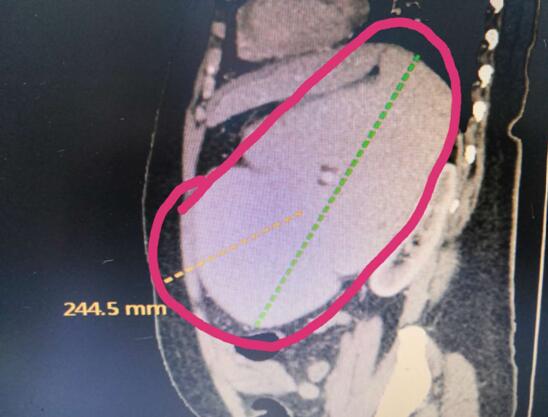

患者B,女,51歲,因牙齦出血1年入院,入院診斷為:乙肝,肝炎后肝硬化,門脈高壓癥,巨脾,脾亢,白細胞、血小板減少,中度貧血。5年前,曾在外院行介入脾栓塞術,脾臟不僅沒有縮小,反而越來越大,脾下緣已經(jīng)超過腹部正中線、抵達臍部,就像幾個月“身孕”的婦女,給病人帶來巨大身心負擔。

(術前腹部CT顯示巨脾)